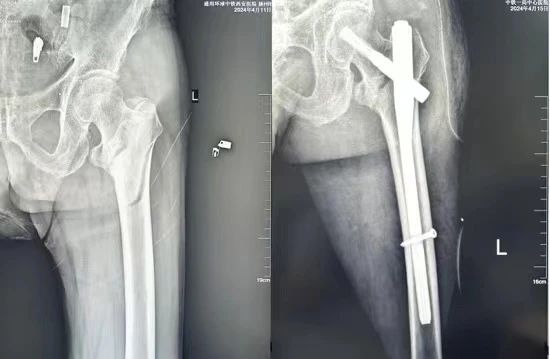

姬传磊接诊后,详细询问病史,并开展了全面检查,影像诊断显示:左侧股骨粗隆间骨折。由于骨折位置特殊,加之老人年过百岁,属于超高龄患者,因此无论是麻醉关还是手术关,对医护团队来说都是极大的挑战。

在手麻科的配合下,姬传磊带领团队迎难而上,化解手术风险,最终成功实施了左侧粗隆间骨折切开复位髓内钉固定术,手术过程顺利。患者术后生命体征平稳,恢复良好,目前已顺利出院。